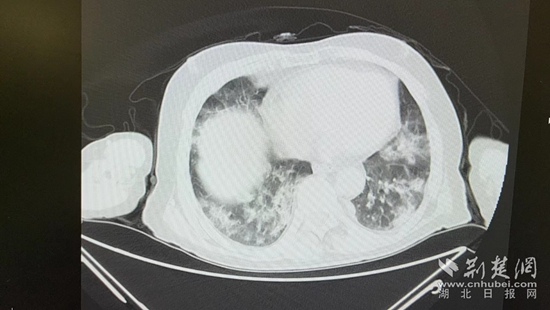

病情的突然惡化,會不會與近期的新冠病毒感染有關(guān)?雖然家屬反映,曾多次在家自測抗原正常,但徐濤還是力排眾議,說服老人進(jìn)行核酸檢測和肺部CT檢查。結(jié)果顯示核酸陽性,60%白肺,結(jié)合老人的表現(xiàn),這正是一例典型的老年人“沉默性肺炎”。

胸部CT片。通訊員 供圖